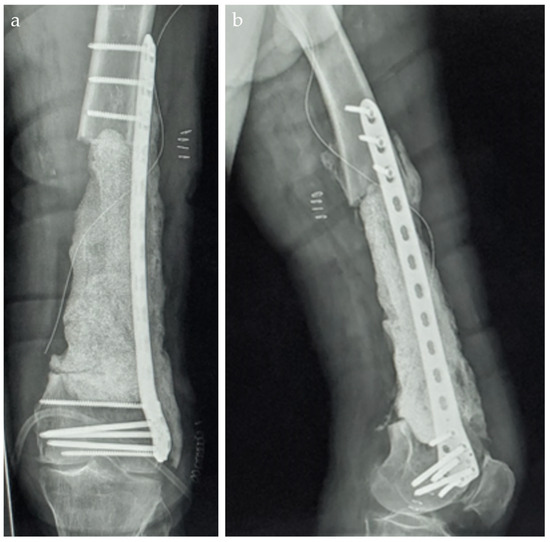

The Use of the Masquelet Technique in the Treatment of Pathological Distal Third Femoral Fracture Secondary to Chronic Osteomyelitis

2. Case Report